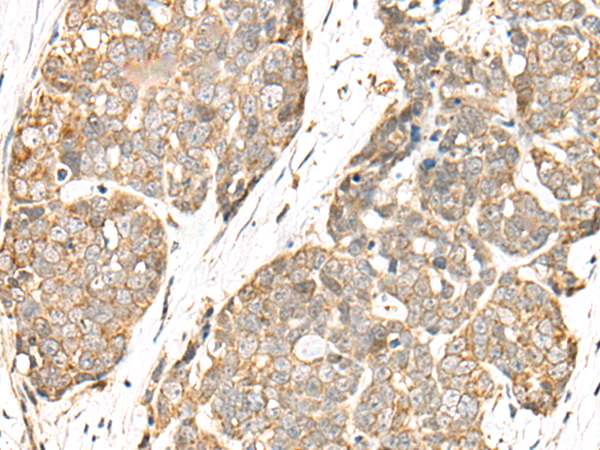

分类: 科研抗体货号: P09424别名: CNB; CNB1; CALNB1应用: IHC反应种属: Human, Mouse, Rat